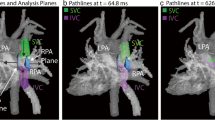

The segmentation of the Fontan circuit was manually performed on the phase with the highest contrast on magnitude-weighted velocity images and/or in the phase contrast MR angiography of the 4D-Flow data using open-source TK-SNAP software [21]. Streamlines quantification and visualization were done using ParaView software [22] and were generated using Paraview software, taking as seed points the planes in the SVC and IVC, with a forward integrator type (Runge-Kutta 4-5). 4D-Flow CMR-derived energetics parameters were evaluated in the Fontan confluence including the IVC-Conduit/tunnel-PA, proximal pulmonary branches, and superior vena cava (Fig. 1). The cutting planes were manually placed around 1.5 cm from the bifurcation.

Caval Flow Distribution

The analysis of the streamlines distribution (excluding the 8 patients with persistent left superior vena cava) revealed a preferential distribution of the right SVC flow for the RPA 62.5 ± 35.4% whereas the distribution of IVC-PA conduit flow to the pulmonary branches was quite symmetric with a mild preferential flow for LPA 52.3 ± 40.6% (Fig. 2). However, in 25 patients IVC-PA conduit flow to LPA was more than the 50 %.

Considering the quantification of streamlines distribution in the whole population, superior vena cava blood flow was predominantly distributed to the RPA, whereas the distribution of the IVC blood flow was quite symmetrical with a mild preference for the LPA. This is in line with previous publication [9, 27].